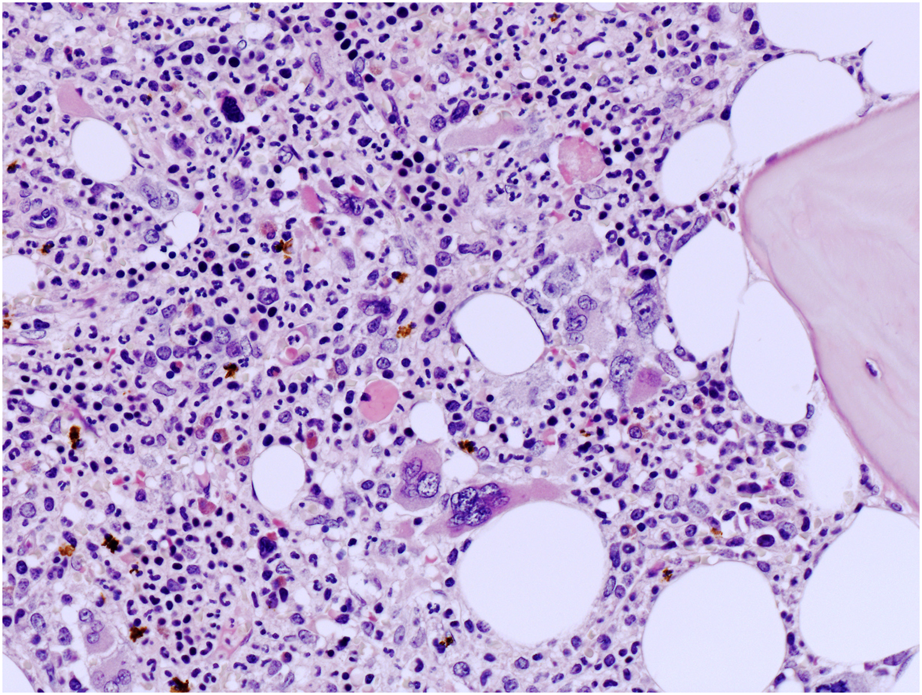

FIGURE 2

High power view of BM biopsy highlighting atypical MKs with non-classical CML features such as large MKs with bulbous nuclei (hematoxylin and eosin, ×200 magnification).

A 45-year-old man was noted to have a new onset thrombocytosis with a PTL count of 526 × 109/L and normochromic, normocytic mild anemia (Hb 10.5 g/dL), whereas the white blood cell (WBC) count (8.02 × 109/L) was within the normal limit with 63% neutrophils, 27% lymphocytes, and 8% monocytes. A moderate splenomegaly was present. Bone marrow (BM) biopsy showed a slightly hypercellular marrow with the prevalence of a normally maturing myeloid lineage; the erythroid lineage in different stages of maturation was reduced; and the megakaryocytic lineage was expanded with even dense clustering of variably sized elements, including megakaryocytes with hyperchromatic nuclei. CD34-positive hematopoietic precursors were not increased. Grade 0 reticulin fibrosis was present. Molecular studies showed wild-type JAK2 V617F and MPL genes, whereas CALR exon 9 mutation type 1 (60% allelic burden) was identified. No BCR::ABL1 rearrangement was found. Karyotype analysis was not available. The combination of clinical, pathologic, and molecular features was in keeping with the diagnosis of MPN and suggestive of PMF, in the pre-fibrotic stage. Anagrelide was initially administered, followed by hydroxyurea (HU) 3 years later with a good hematological control of the disease. After 11 years, a progressive increase in the WBC count was noted (57 × 109/L), with mild anemia (Hb 9.2 g/dL) and normal PTL count (177 × 109/L). Splenomegaly (18 cm diameter) was detected. BM biopsy showed a markedly hypercellular marrow (95% cellularity) with prevalent and normally maturing granulopoiesis, the erythroid lineage was reduced with features of dyserythropoiesis, and megakaryocytes were increased in number with large-sized elements along with small-sized cells with hyperchromatic nuclei and evident dense clustering (Figures 1, 2). Grade II reticulin fibrosis was present. Repeated molecular studies confirmed CALR exon 9 mutation (allelic burden 40%) and JAK2 V617F and MPL negativity, whereas the BCR::ABL1 rearrangement was identified. RT-PCR identified the BCR-ABL1 fusion transcript of the p210 variant (allelic burden 88%). Karyotype analysis detected a 46XY karyotype with t (9:22) (q34; q11) translocation. Altogether, the clinicopathologic and molecular findings supported the diagnosis of PMF (with CALR mutation) and subsequent occurrence of the BCR::ABL1 rearrangement, therefore, interpretable as the coexistence of a Ph-negative MPN with CML. Tyrosine-kinase therapy (TKI) with nilotinib (600 mg/die) associated with ruxolitinib was given. After introduction of TKI treatment, the patient achieved a deep molecular response (DMR) within 6 months, with negativity of BCR-ABL1 but persistence of CALR type 1 mutation (allelic burden 45%). The patient is still on combined treatment (ruxolitinib plus nilotinib) with DMR and good control of disease despite persistence of CALR mutation, 7 years after CML occurrence.

The pathologist may suspect the coexistence of Ph-negative MPN and Ph-positive CML from a close examination of BM histology. Non-clustering small MKs, the so-called dwarf MKs, are normally found in CML, whereas large and clustered MKs are common in Ph-negative MPNs.

Therefore, the identification of large MKs with hyperlobulated nuclei in BM of CML patients should prompt additional genetic testing including CALR mutations to exclude the coexistence of a Ph-negative MPN. Some cases of our literature review showed unusual MK morphology with composite features (hybrid MKs with both small and large forms), which should represent a clue for molecular testing.